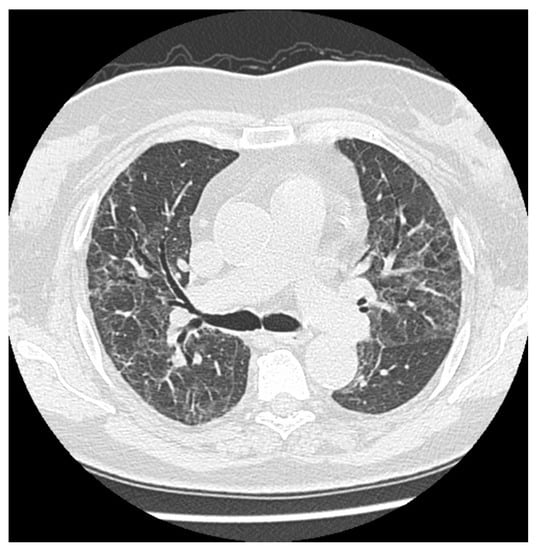

On follow-up CT images, 94.9% of patients still exhibited some persistent radiological abnormalities. The most frequently observed changes at mean 5 months after COVID-19 pneumonia were ground-glass opacities (GGO) (74.4%), reticular pattern (64.1%), fibrotic changes (53.8%) (Figure 1), nodules (33.3%), bronchiectasis (15.4%), vascular enlargement (10.3%), and cavitation or air bubble signs (5.1%) (Figure 2). Table 4 shows the complete distribution of lung abnormalities in both severe and moderate groups, as well as the clinical characteristics of patients. No significant differences were noted between various sex subgroups, nor between the severe and moderate progression of the illness. However, the prevalence of reticular pattern, fibrosis, bronchiectasis, and vascular enlargement was slightly higher in the severe group of patients compared to the moderate group.

Figure 1. Some persistent fibrotic lines and ground glass opacities in a male patient 6 months after the onset disease.